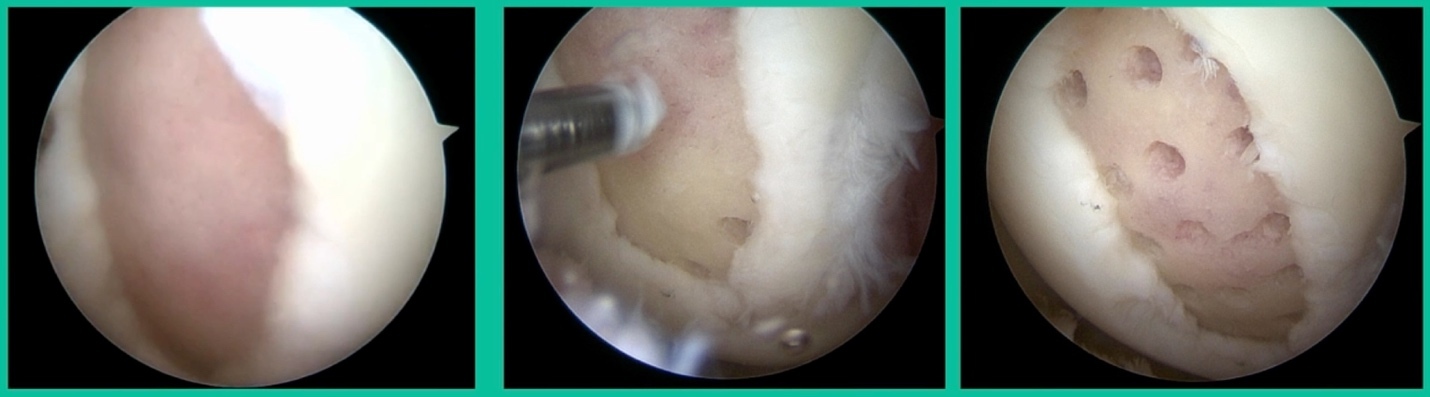

I thought I might be able to fix it. I had the conversation with the family, get in there, started taking it apart with a Vanguard elevator grasper. Behold, it’s really just cartilage fragments (Figure 2).

There’s two or three of them. We debrided it. It felt normal in six weeks, no complaints in three years. What are the results of juvenile debridement? They’re actually profoundly good. You would never expect this in the scheme of things, but the natural history of removing the piece is actually very good in the juvenile patient. However, once again, fix it if you can. Debride it, if you can’t. If they get symptoms, we restore it, and then never leave unstable fragments.

We get in there, it’s delaminated, not much bone, nothing to fix in my mind, and so we drilled it.

How do these do? There’s actually reasonable data for marrow stimulation for OCD. But if you have the option for small defects, I would prefer an osteochondral allograft over microfracture based on the literature. That’s the take-home. Marrow stimulation, if you do it, you’re probably better off drilling it. We showed that we could reduce revision rates with marrow stimulation by two-thirds if you drill it versus use a microfracture awl.

Worsening over the last two years, has effusions but no locking, and has a large area of involvement that appears unstable. This is the classic fixation. If you can do this, this is the holy grail. Remember, fracture non-union: you elevate it, debride the base, get rid of any unstable fragments, just take them out, and preserve the major fragment. I’ll use a microfracture awl, but most commonly now I’ll use a pick or a pin, and I’ll drill it. I use two to three metal screws. I bury their heads, and then I come back at eight weeks after being non-weight-bearing, and pull the screws out.